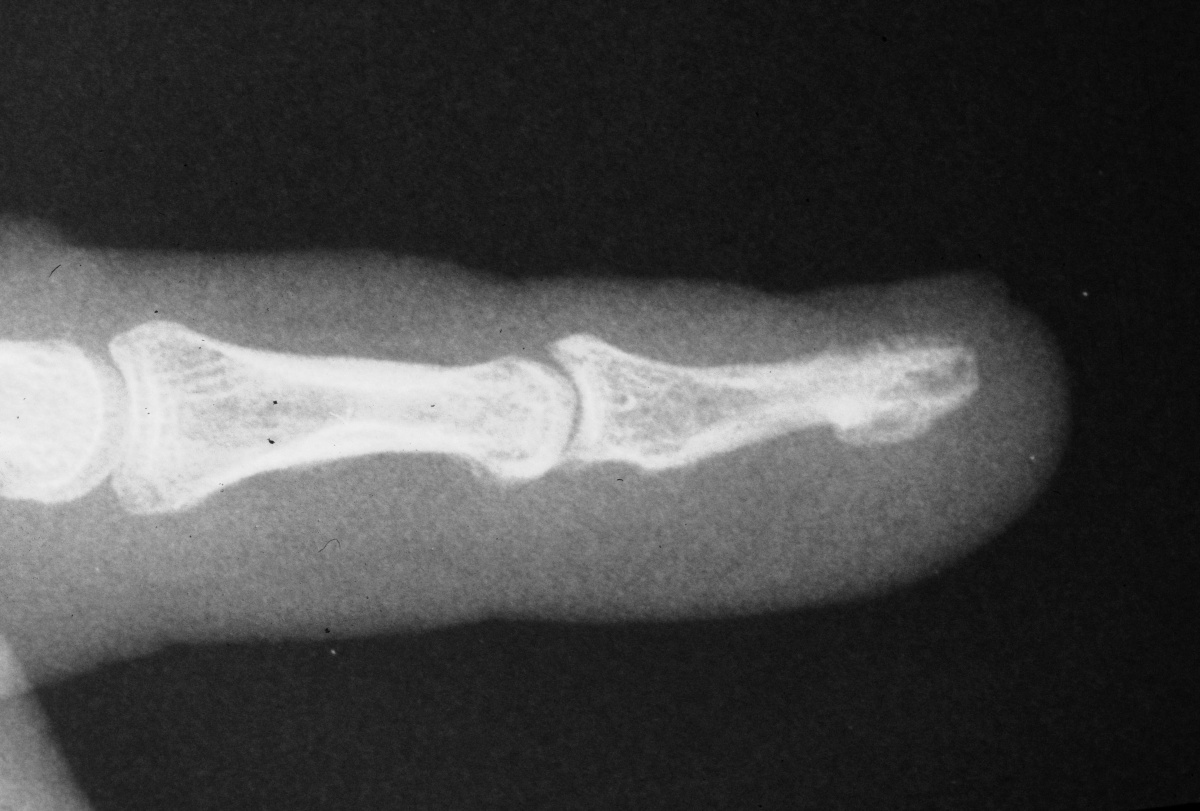

| Case 1. 6 week old grossly unstable distal phalanx fracture. Fracture reduced through a midline palmar approach and stabilized with extraarticular nonparallel Kirschner wires. |

| The K-wires were

bent to form a zone of overlap which was bonded

together with thermoplastic splint material. |

| Pins were removed

at 5 weeks with uneventful fracture healing. |